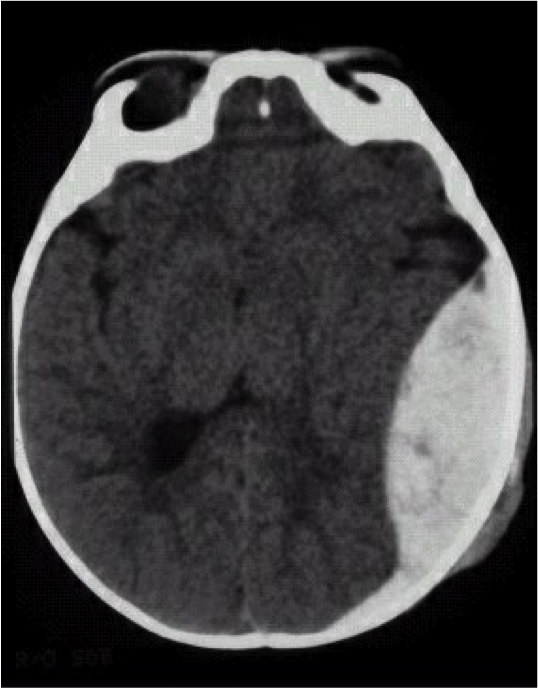

What is shown?

Epidural hematoma